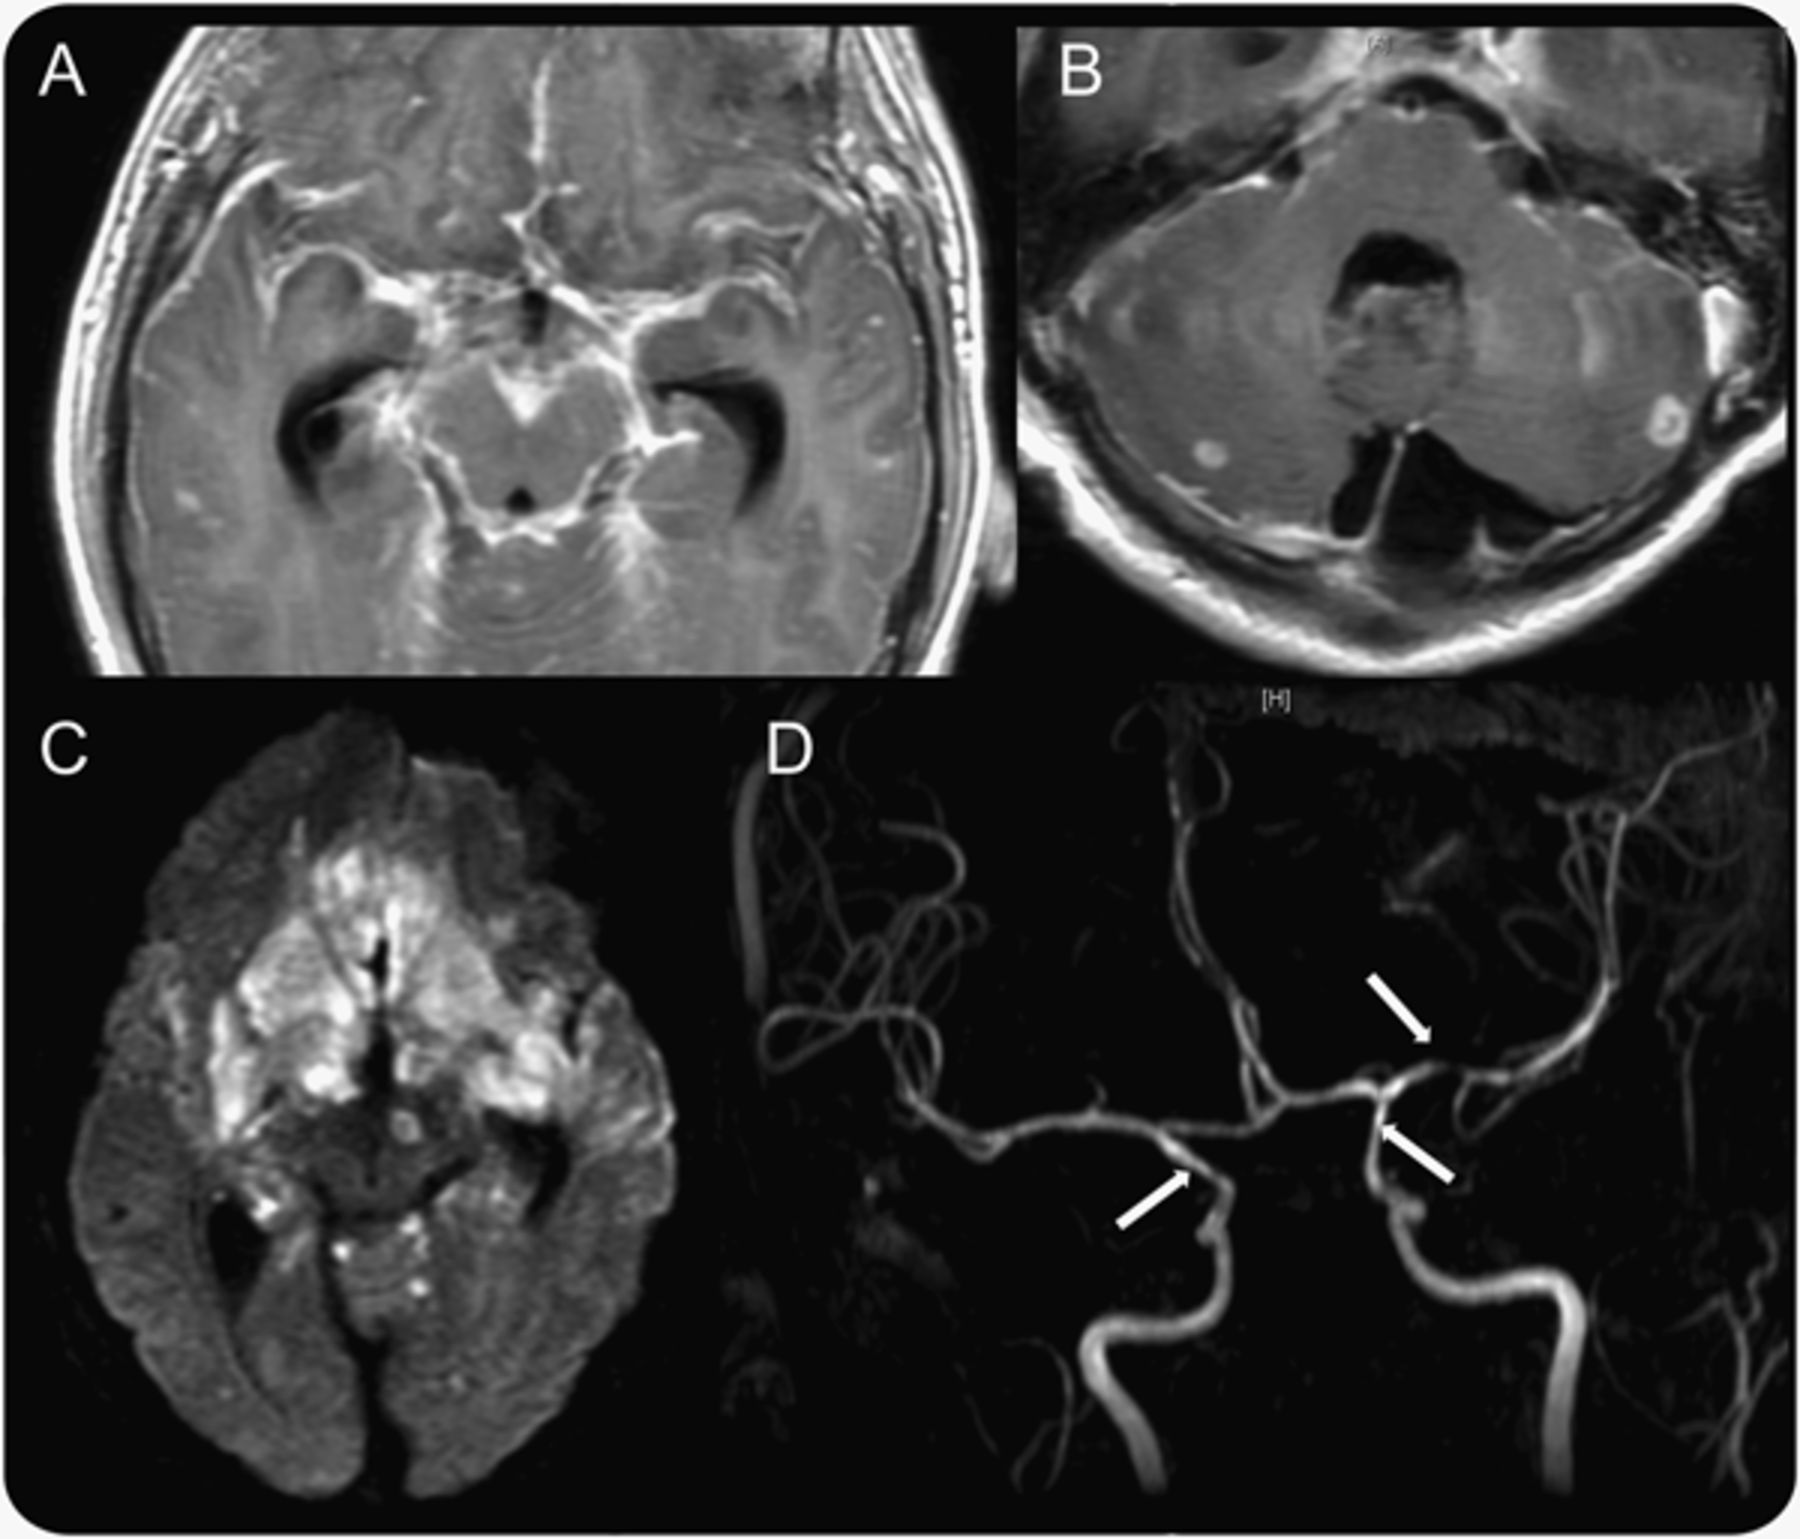

(A和B)与钆对比显示蛛网膜增强和小脑ring-enhancing疫源地兼容小脓肿。(C)限制扩散的双边额叶、基底神经节和pontomesencephalon兼容广泛梗塞。使用三维飞行时间(D)磁共振血管造影成像显示颈内动脉狭窄的远端和近端左大脑中动脉(箭头),以及远端和脑动脉分支的前部和中部与血管炎兼容。

提交给当地的一个21岁男子急诊科5天的头痛、无趣,枕,双边、nonthrobbing,逐步恶化。它与轻度发烧、畏光和颈部疼痛和僵硬。他没有历史的头痛、慢性疾病,最近的疫苗,皮肤疹、咳嗽、腹泻、关节痛、肌痛。他来自厄瓜多尔和已经在美国生活了不到1年。他被监禁在厄瓜多尔。舌下温度对录取为102.6°F。其他生命体征都在正常范围内。在体检,他看上去很瘦弱但不是恶病的。他有假性脑膜炎和畏光,但没有视神经乳头水肿和他的精神状态预警和专注。没有焦神经赤字。 CSF contained red blood cells: 24 × 103/μL;白细胞:85 /μL(淋巴细胞主要);蛋白质:128 mg / dL;和葡萄糖:48 mg / dL (CSF /血清葡萄糖比= 0.53)。CSF革兰氏染色剂和文化,产后抑郁症测试,血液和尿液文化都是负面的。CT扫描的头一天承认完全是正常的。没有钆对比MRI显示一个点状的T2 hyperintensity在左额叶室周的白质。胸片是清楚的。他惯用的万古霉素、头孢曲松钠和无环鸟苷。糖皮质激素并没有给出。 The patient did not improve with antibiotics and continued to be intermittently febrile. On day 5, he became abruptly more somnolent, then comatose, opening eyes only to pain, his pupils were 5 mm and reactive, he had intact brainstem reflexes, withdrawing both arms and legs. Emergent head CT showed development of hydrocephalus and a ventriculoperitoneal shunt was emergently placed. The neurologic examination did not improve after shunt placement, and repeat head CT showed increased hydrocephalus with bilateral cerebral infarcts. On day 11, he was transferred to Columbia University Medical Center for intensive care. He was febrile and comatose. He did not open his eyes to pain, pupils were 7 mm minimally reactive, brainstem reflexes were intact, and he exhibited extensor posturing to pain. Mannitol was given, corticosteroid therapy was started, and an extraventricular drain was placed. The next day, his right pupil was 8 mm and nonreactive. MRI showed diffuse contrast enhancement of the arachnoid, extensive infarction of basal ganglia, midbrain, and pons, and small ring-enhancing lesions in the cerebellum (图1中,模拟)。重复腰椎穿刺显示红细胞:550×103/μL;白细胞:250 /μL(14%的中性粒细胞,80%的淋巴细胞,单核细胞6%);蛋白质:65 mg / dL;和葡萄糖:< 10 mg / dL (CSF /血清葡萄糖比= 0.08)。CSF测试隐球菌弓形体病是负的。脑脊液抗酸杆菌涂片(AFB) -×2,和CSF核酸扩增试验也为阴性肺结核。血清HIV检测是负面的。直到14天之后首次表示和3天转移到重症监护室公开治疗后终于开始,因为在MRI显示梗塞的模式基脑膜炎和他没有改进的广谱抗生素。同一天,第一个涂片是阳性痰空军基地,作为日常痰涂片空军基地都成功。肺结核痰核酸扩增是积极的,但从脑脊液持续消极。每日便携式胸片正常(阅读可能肺不张),但胸部CT显示致密合并左肺和在两肺弥漫性结节性的透明。两天后,他头痛的发作只有21天后,病人死于心肺骤停的次要transtentorial脑疝。13天后,脑脊液文化变得积极结核分枝杆菌对链霉素、异烟肼、乙胺丁醇,利福平,吡嗪酰胺。